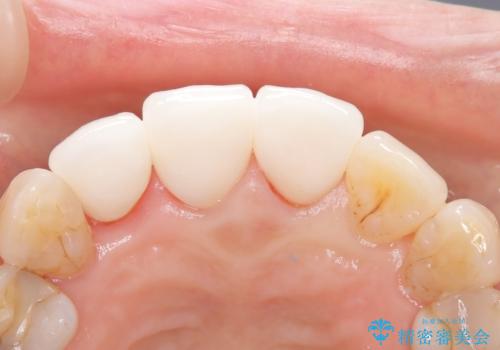

【外傷歯】根管治療から被せ物まで。

- 外傷により他院で治療中に転院を希望され受診されました。

前医では、抜歯も提案をされていましたが適切に治療を行うことで歯を保存することができました。

歯槽骨内水平性歯根破折は、抜歯の適応ではありません。

セラミック治療の注意事項(リスク・副作用など)

- 天然歯を削ります

- 硬い素材は天然歯を傷つけてしまう場合があります

- かみ合わせや歯ぎしりが強すぎる方はセラミックが割れてしまう可能性があります

- 自費診療(保険適用外治療)となります